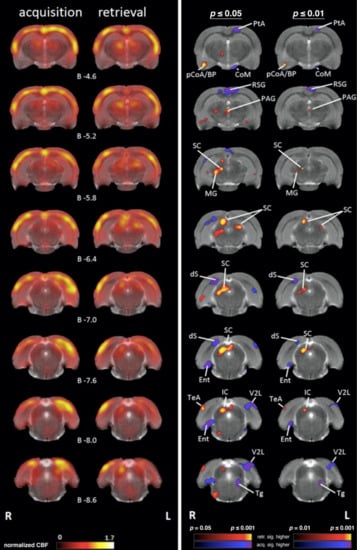

4.1. Comparing Regional Cerebral Blood Flow during Acquisition and Retrieval

4.1.1. Sensory/Motor Cortex

4.1.2. Subcortical Systems

4.1.3. Association and Prefrontal Cortices

4.1.4. Medial Temporal Lobe (MTL)/Limbic Regions

4.1.5. Limbic Output Regions